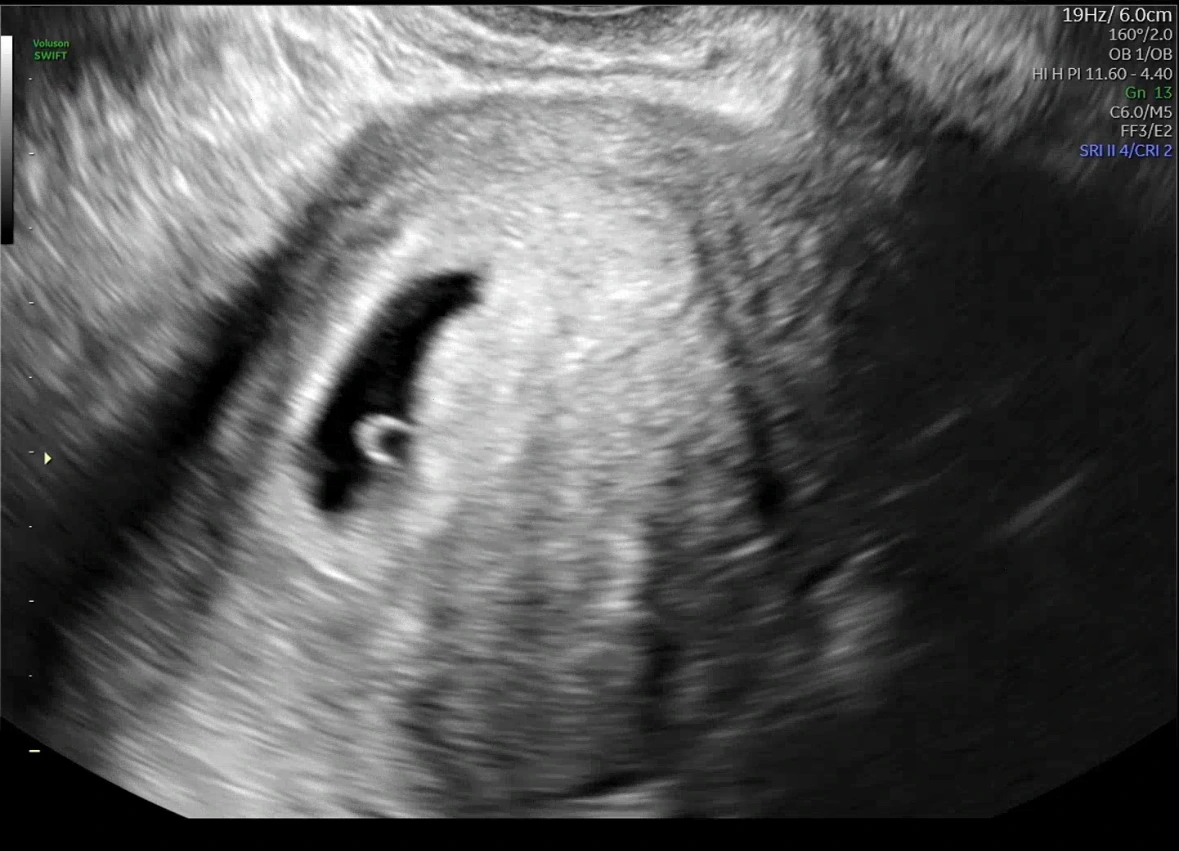

“여기 아기집 보이시죠~? 축하드립니다. “

산부인과 선생님의 컨펌이 났다! 나 정말 임신했잖아!! 우리 이제 정말 부모가 되는거잖아!!!